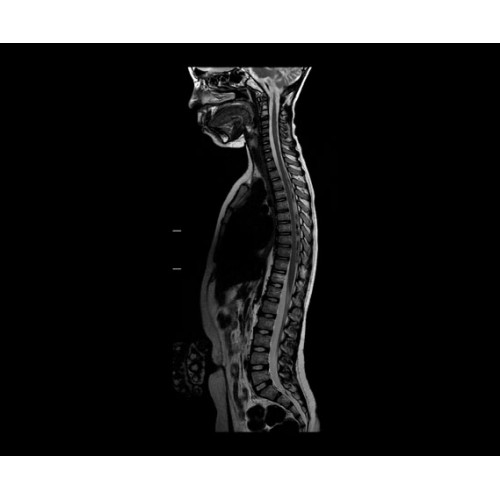

SIGNA PET/MR 3.0T — это гибридная система, в которой совмещаются две принципиально разные технологии — магнитно-резонансную томографию (МРТ) и позитронно-эмиссионную томографию (ПЭТ). Система отличающийся высокой чувствительностью и эффективностью и предназначена для диагностики в области онкологии, неврологии, кардио-васкулярных исследований, исследований воспалительных процессов.

Компания GE Healthcare представляет революционную, полностью интегрированную систему SIGNA PET/MR1, в которой сочетаются времяпролетная технология (TOF) и возможности напряженности магнитного поля 3.0 Тл. Мы поможем вам поднять исследования на более высокий уровень. SIGNA PET/MR позволяет достичь впечатляющей точности и скорости исследований, а благодаря новейшей технологии реконструкции Q.Clear2 качество изображений улучшается в два раза. Кроме того, в систему включен полный набор клинических приложений и гибких катушек для проведения любых видов исследования, открывая для вас возможности визуализации, о которых вы даже не догадывались.

Система SIGNA PET/MR предлагает впечатляющие клинические возможности и открывает доступ к наиболее полным пакетам программных приложений.

Стандартный пакет приложений SIGNA Works позволит вам достичь желаемых результатов в клинической практике благодаря набору высокоэффективных средств визуализации. Программные приложения, входящие в состав данных клинических пакетов, включают широкий спектр контрастов, функции обработки 2D- и 3D-данных, а также возможность коррекции артефактов движения. SIGNA Works предоставляет набор инструментов, необходимых для проведения эффективного клинического исследования.